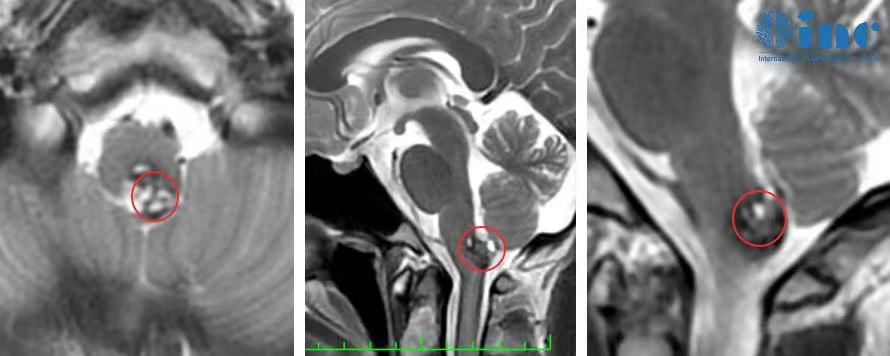

脑干延髓是心跳、呼吸等关键生命中枢,神经核团高度密集,脑干海绵状血管瘤有反复出血造成肢体瘫痪、呼吸困难无力甚至昏迷等风险,手术一直以来都是难题。

整个做完以后包括片子拍出来以后,我也给我们那的神经外科医生看。一看,他说:唉呀,真的很神奇,做的这么干净,做的这么好。关键是恢复的也这么快,1天就出ICU了,而且神志这么清晰。我儿子就继续给他打电话,他说不可能吧。

术后第一天巴教授ICU查房,阿朔意识清楚、对答入流、四肢活动灵活